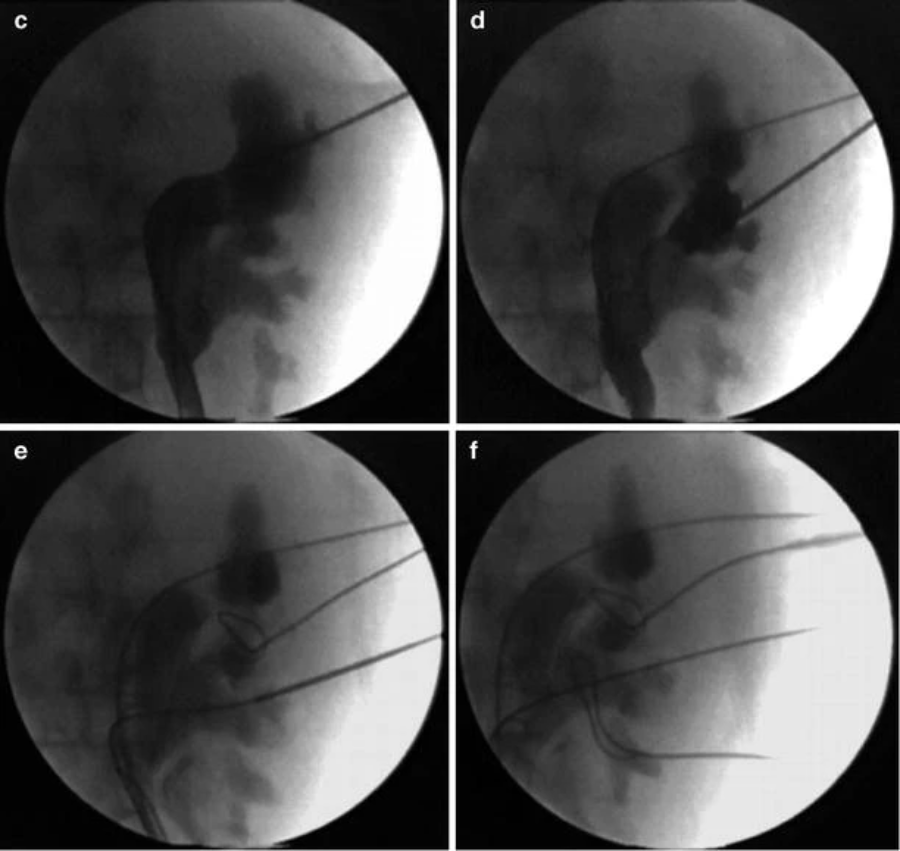

尽管有所有这些技巧可以通过单个肾造口术改善取石效果,但重要的是要记住,如果在无法触及的花萼中有大量结石,第二次肾造口术仍然是最快和最有效的取石方法清除。在预期使用两个或更多束的情况下,我们建议在扩张任何束之前,在计划进入的每个盏上进行初始穿刺和导丝放置(图41.7a-f)。通过在每次穿刺的透视引导下使用造影剂,显着有助于多道 PCNL。由于 Amplatz 鞘的渗漏和与管道相关的外渗,在管道扩张后,造影剂的使用变得困难。对于随后不需要的任何预先计划的管道,只需在程序结束时移除导丝。

右经皮肾镜取石术 (PCNL) 中所有潜在束的预扩张导丝放置,用于鹿角。( a ) 普通 KUB 显示双侧鹿角形结石。( b ) 静脉尿路造影 (IVU) 胶片。( c ) 右侧 PCNL 的初始导丝放置。( d ) 第二次导丝放置。( e ) 第三次导丝放置。( f ) 第四次导丝放置